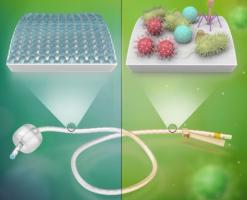

Actualité publiée le 30/06/2025IAS : Des pics de graphène bactéricides contre le biofilm

Actualité publiée le 12/06/2018CATHÉTERS, IMPLANTS : Des nanopointes de graphène contre les pathogènes

CATHÉTÉRISME : Un cathéter intelligent qui prévient l’infection sanguine